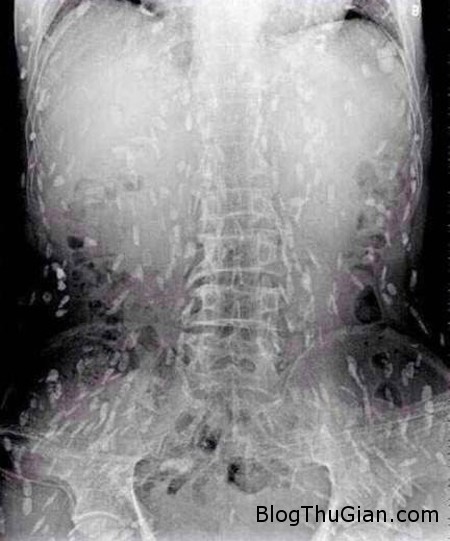

Tuy nhiên, do bệnh tình đã bước sang giai đoạn nghiêm trọng nên người đàn ông tiếp tục được chuyển tới Bệnh viện Nhân dân số 8 ở Quảng Châu để điều trị. Kết quả chụp X-quang cho thấy, những đốm trắng nhỏ xuất hiện lấm chấm khắp cơ thể chính là sán.

Những chấm trắng xuất hiện trên hình chụp X-quang là sán.